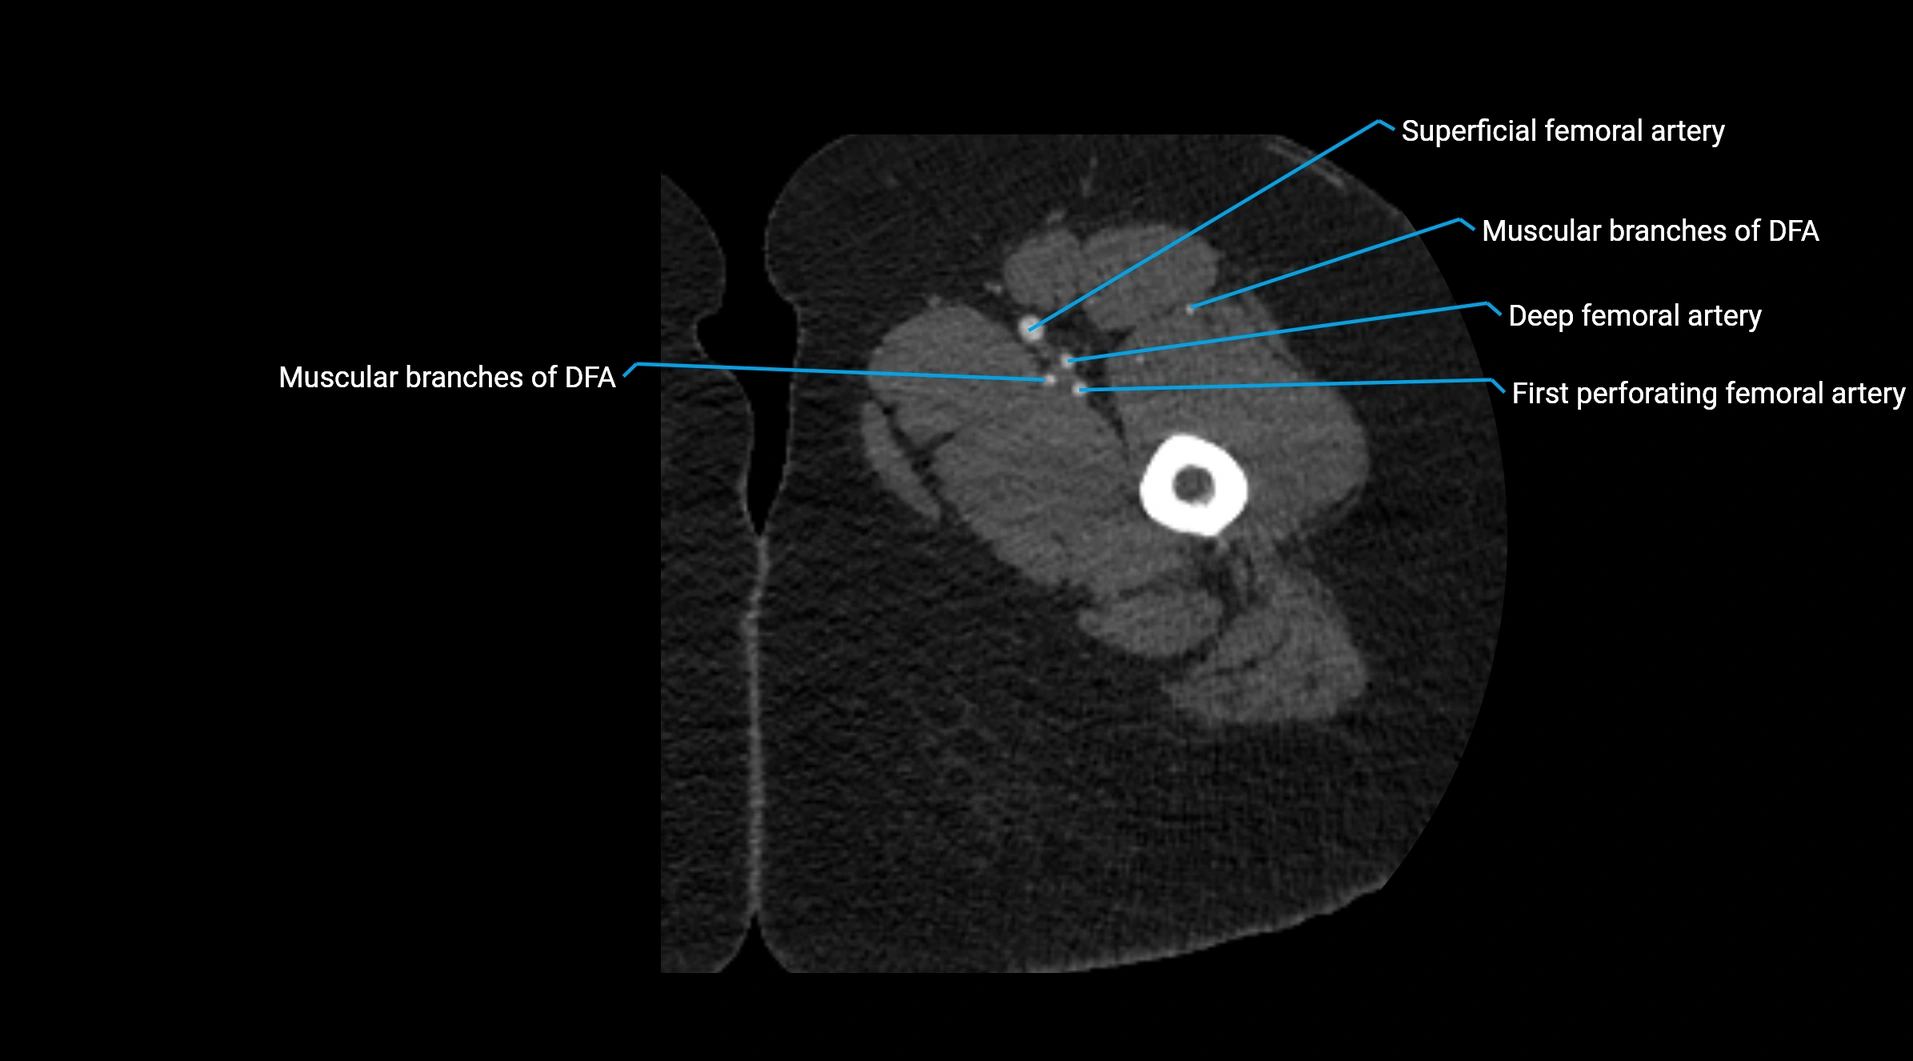

CT images

image

Contrast-enhanced CT (CTA):

• Gold standard for abdominal aortic imaging

• Provides excellent detail of lumen, wall, aneurysm, thrombus, and branch vessels

• Multiplanar and 3D reconstructions help in aneurysm measurement, stent graft planning, and dissection evaluation